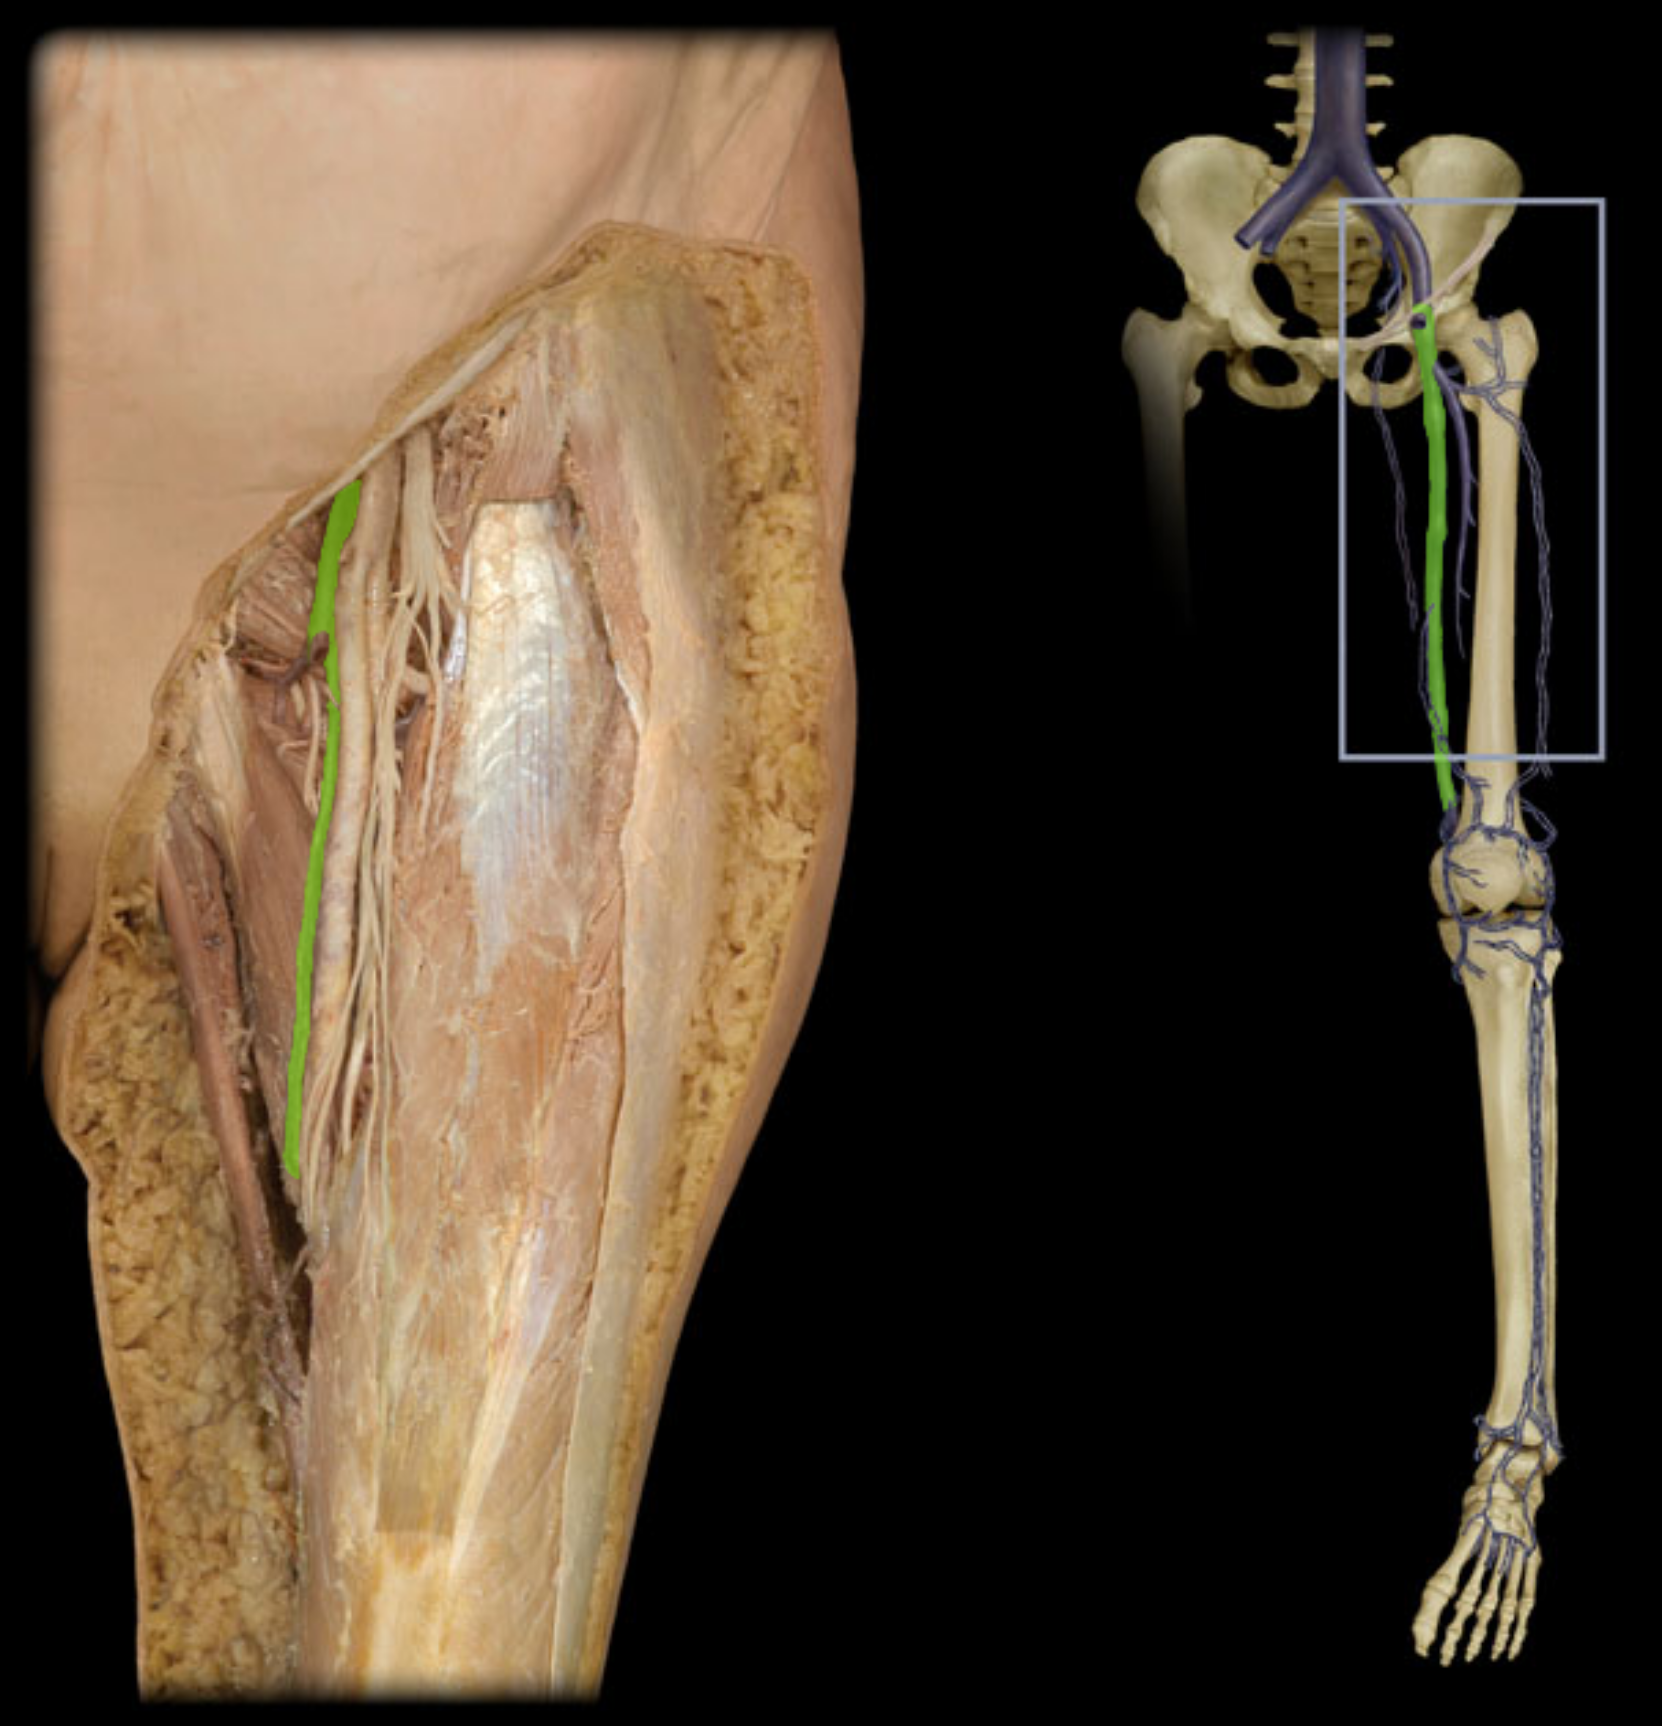

Femoral v.

Great saphenous v.